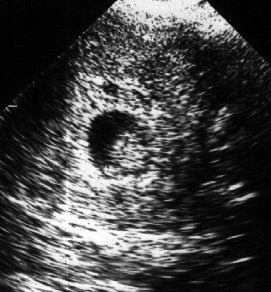

7 неделя беременности

Длина эмбриона достигает 5 мм, тело приобретает С-образную форму. Сердце начинает подразделяться на камеры. Оно бьется со скоростью 100-160 ударов в минуту, то есть в 1,5-2 раза чаще, чем у взрослого человека, а кровь плода начинает циркулировать по всему телу. Начинается формирование пищеварительной системы. На этом этапе закладываются основные ее части: печень, желудок, кишечник, поджелудочная железа.